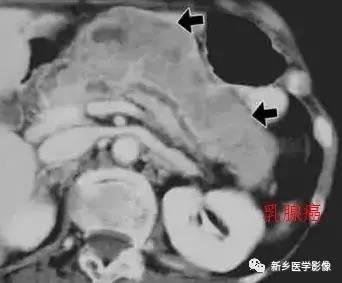

四、胰腺转移瘤

胰腺转移瘤在临床上较为少见, 1000 例恶性肿瘤尸检中,仅3 %有胰腺转移。原发肿瘤可为肺癌、乳腺癌、肾细胞癌、卵巢癌、结肠癌、黑色素瘤等。胰腺不是肿瘤转移的常见部位。胰腺转移瘤的影像学表现与原发肿瘤有一定关系, 可表现为乏血供或富血供胰腺肿块, 有时E RCP 可示主胰管内充盈缺损。转移

瘤的影像学表现少有特异性,且发病率很低,故诊断常依靠原发肿瘤的确诊以及胰腺病变的细胞学检查。